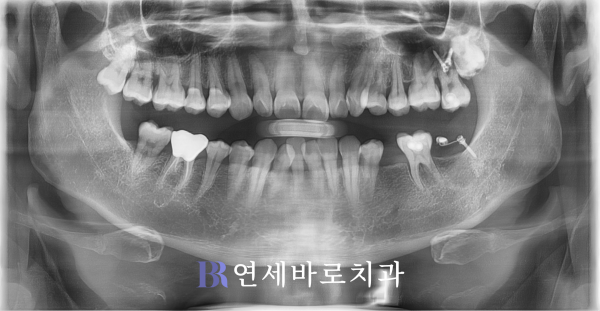

그래서 추가적인 상담 끝에

임플란트가 식립되기 전,

부분교정을 진행하였습니다.

쓰러진 어금니를 바르게 세워

올바른 각도로 일으켜주었고,

상악 대합치를 위로 올려주는

상방견인이 이루어졌습니다.

어느 정도 시간이 지나고서

사랑니를 발치하였습니다.

이렇게 매식체를 심기 위해서

적절한 공간을 만들었는데요.

부분교정이 마무리된 뒤에는

본격적으로 매식체를 심고

골유착이 충분히 일어난 후

치아 머리를 결합했습니다.

위의 사진은 최종적으로

모든 치료가 종료된 뒤에

확인 차 촬영한 것인데요.

하악 제1대구치의 앞뒤로

빈 곳이 잘 수복되었습니다.

뿌리 부분과 주변 골조직의

골융합도 안정적인 수준이죠.